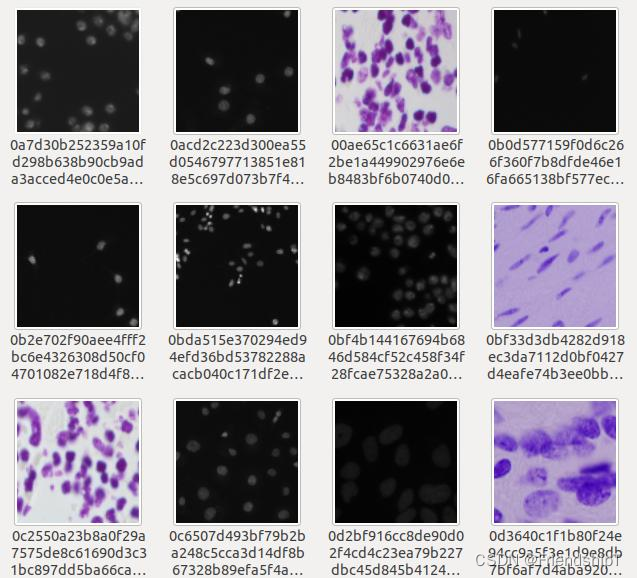

准备数据集

- 原图